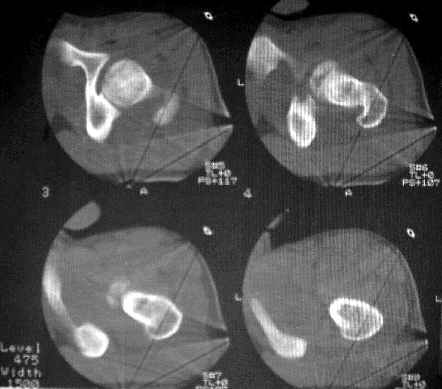

Уважаемые коллеги! Спасибо всем, кто откликнулся на обсуждение. На сегодня доделаны боковые снимки и КТ. Компьютера с возможностью 3D реконструкции на Камчатке нет. Официальное заключение по имеющимся сканам: имеется оскольчатый перелом головки бедра с фрагментацией ее передне-нижнего отдела. Соотношения в суставе в настоящее время правильные. Кзади и выше него в мягких тканях - отдельно лежащий костный фрагмент 15х25 мм (вероятно от головки).

Досылаю на форум КТ и R-граммы. У самого, откровенно говоря, сомнения остаются относительно того, что это не фрагменты вертлужной впадины. В последнем случае, думаю надо оперировать, а если это фрагменты головки из ненагруженной зоны - то не уверен. Какие есть мнения, в том числе и по срокам рагрузки сустава? Главный травматолог Камчатского Военно-морского госпиталя Булахтин Юрий Алексеевич Больного сейчас ничего не беспокоит. Уложен на щит, иммобилизация деротационным сапогом.

КТ1

КТ2

КТ3